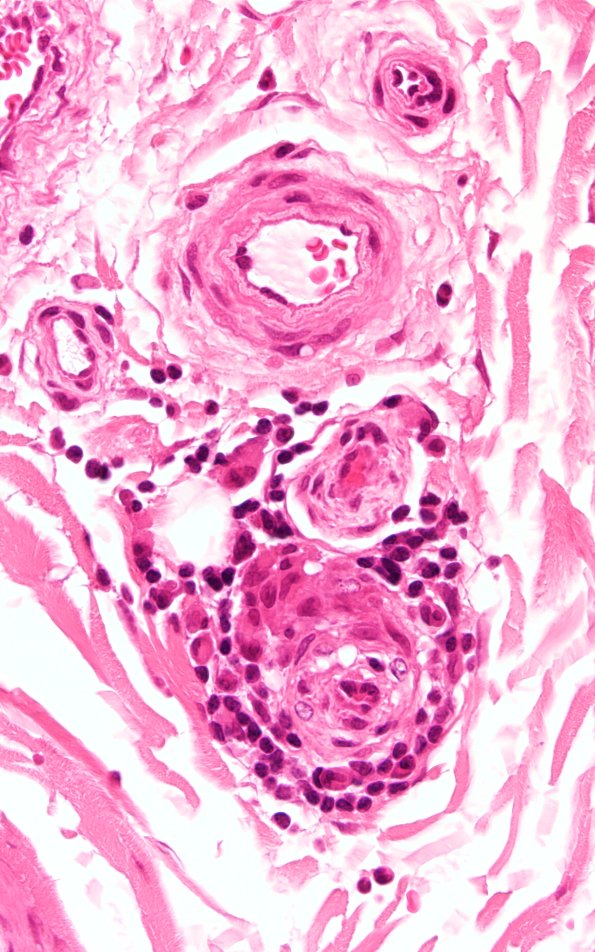

1A3 Anti-MAG Neuropathy (Case 1) H&E 60X 1

The inflammatory cells in this case include lymphocytes and, unusually, plasma cells. (H&E)